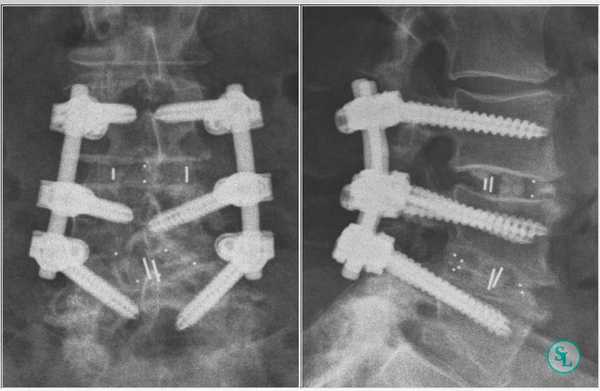

Рентгенограммы полученные после трансфораминального спондилодеза поясничного отдела позвоночника.

В. Рентгенограмма в положении стоя в боковой проекции — спондилолистез L3-L4 первой степени и дегенеративные изменения замыкательных пластинок. Послеоперационные рентгенограммы в прямой (слева)

и боковой (справа) проекциях после прямого бокового межтелового спондилодеза L3-L4 и минимально инвазивной транспедикулярной стабилизации позвоночника. Аксиальный МР-скан в режиме Т2:

Интраоперационные рентгенограммы установки кейджа ROI-A с интегрированной с ним пластиной.

А. Введение импланта в межтеловое пространство L4-L5.

Б. Рентгенограмма после установки кейджа и стабилизации его безвинтовыми пластинчатыми фиксаторами.